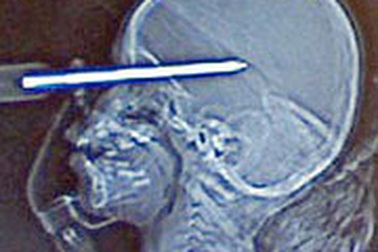

Soi gương mới phát hiện thấy tua-vít đâm xuyên tránMột nam thanh niên ở Ba Lan bị một chiếc tua-vít đâm xuyên qua trán đi thẳng vào đầu. Điều đặc biệt, thanh niên này chỉ phát hiện thấy tua-vít khi anh ta nhìn vào một tấm gương chiếu hậu ở xe hơi.

2 tuổi, thoát chết sau khi bị tua vít xuyên vào đầuĐiều kỳ diệu đã diễn ra với bé gái Teagan Gislason, 2 tuổi sống tại bang Minnesota, Mỹ khi em vô tình bị một chiếc tua vít xuyên thẳng vào đầu. Các bác sĩ đã mất 4 giờ để lấy ra chiếc tua vít mà không cần phẫu thuật và Teagan đang hồi phục rất nhanh chóng.